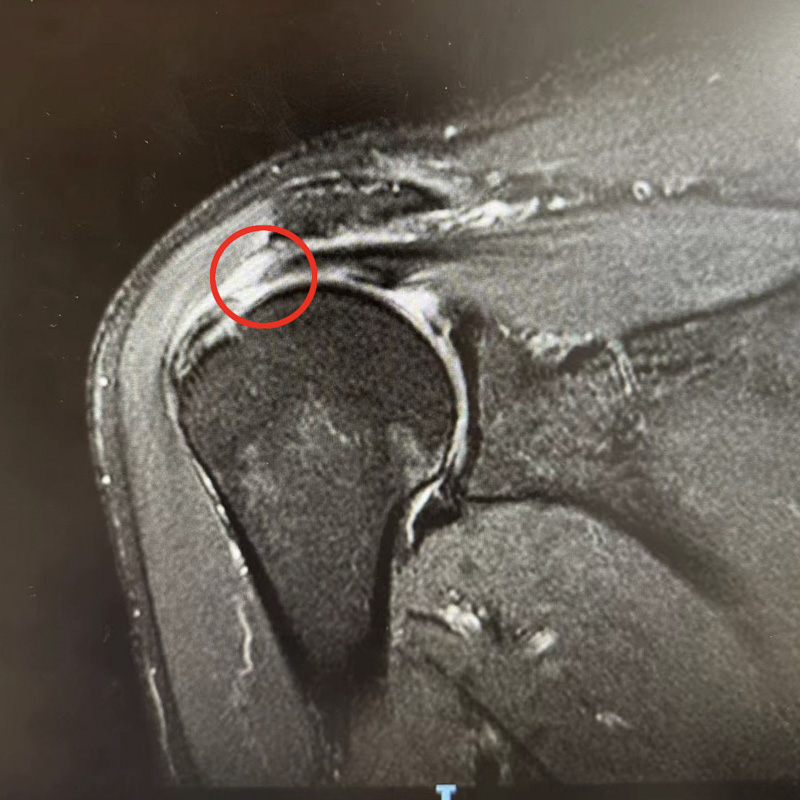

在郭老伯的比劃和親屬的手語(yǔ)翻譯下,運(yùn)動(dòng)醫(yī)學(xué)科副主任韋釗嵐慢慢了解了患者的病情,初步判定為肩袖損傷。此后的磁共振檢查也驗(yàn)證了她的判斷,老人的肩袖損傷已達(dá)到十分嚴(yán)重的程度。

對(duì)于肩袖損傷,韋釗嵐醫(yī)生建議盡早治療。輕微的肩袖損傷,通過(guò)正規(guī)的保守治療能獲得較好療效,保守治療無(wú)效的,應(yīng)盡早行手術(shù)治療。針對(duì)郭老伯的情況,運(yùn)動(dòng)醫(yī)學(xué)科團(tuán)隊(duì)在關(guān)節(jié)鏡下對(duì)撕裂的岡上肌腱進(jìn)行復(fù)位縫合固定,手術(shù)非常成功。